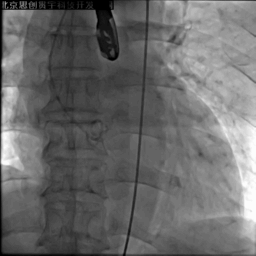

主动脉根部造影

20mm球囊预扩

第一次释放,瓣膜位置偏高